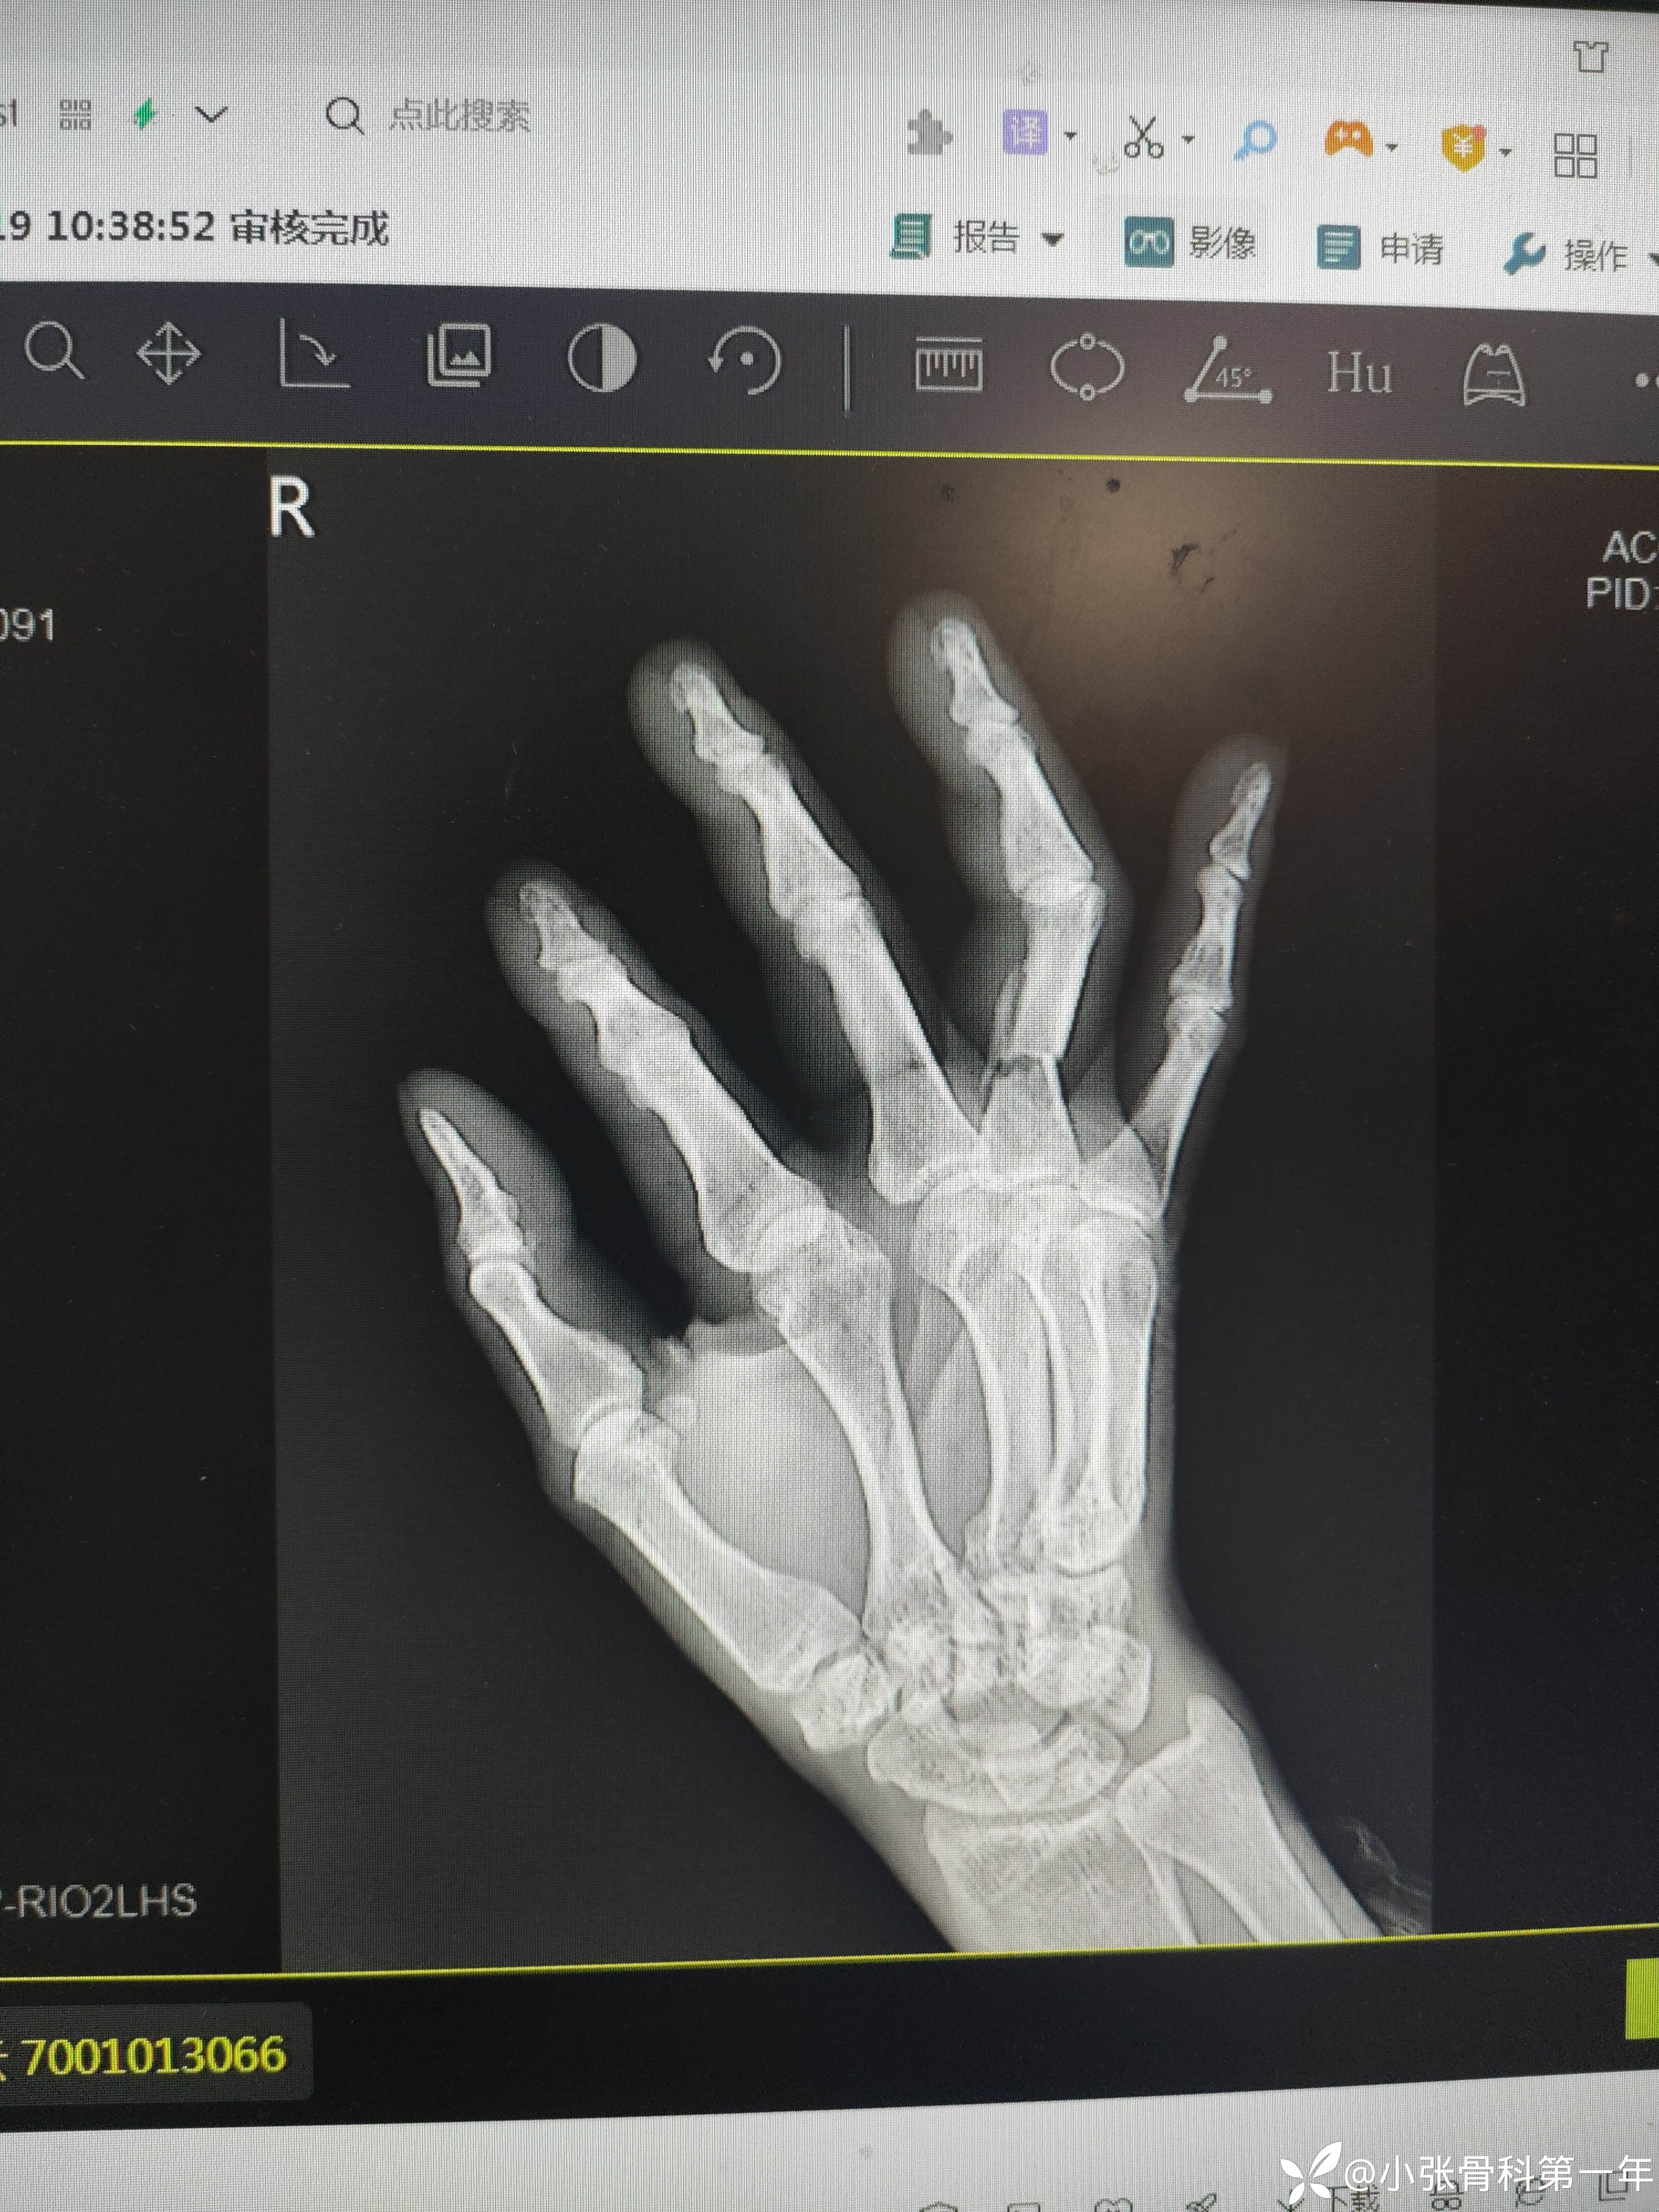

患者中老年男性,58岁,夹伤致右手环指疼痛流血伴活动受限3小时入院。

急诊闭合复位克氏针内固定术